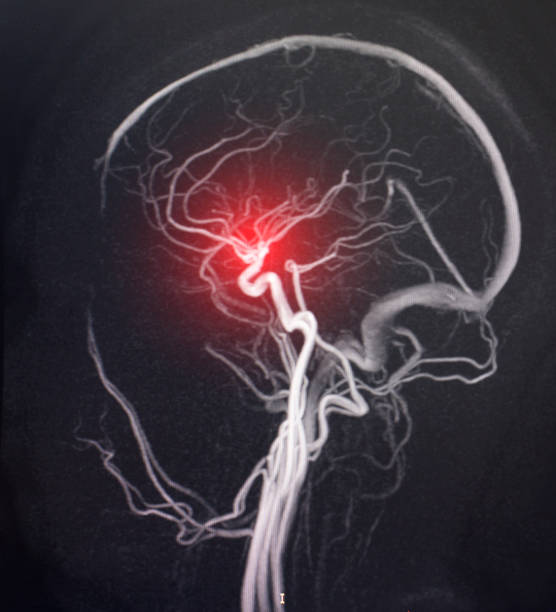

🟢 뇌경색이란 무엇인가요?

뇌경색은 뇌혈관이 막히면서 해당 부위에 혈액이 공급되지 않아 뇌세포가 손상되는 질환이에요.

**‘허혈성 뇌졸중’**이라고도 하며, 전체 뇌졸중의 약 **70~80%**를 차지할 만큼 흔한 형태입니다.

보통은 고혈압, 당뇨, 고지혈증, 흡연, 심장질환 등이 주요 원인으로 작용하죠.